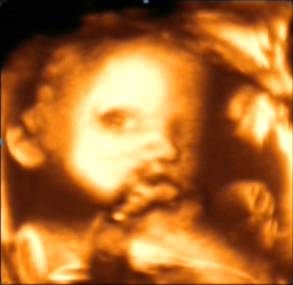

四维彩超就是四维成像技术(4D),能直观、立体显示人体器官的三维结构及动态、实时地观察立体结构,而以往的二维成像技术只能显示人体器官的某一切面。4D技术的应用,为临床超声诊断提供了更丰富的影像信息,减少了病灶的漏诊,提高了诊疗质量。适用于心脏、肝、胆、脾、胰腺、妇产科、外周血管、表浅器官(如眼球、甲状腺、乳腺、阴囊等)软组织各种疾病的检查。尤其在妇产科方面,对胎儿进行超声检查能立体显示胎儿的颜色、面、各器官的发育情况,甚至胎儿在母体里的状态也可以观察到;对胎儿畸形,如唇裂、腭裂、骨骼发育异常、心血管畸形等能早期诊断。

四维彩超还能让准爸爸和准妈妈们了解宝宝在母体里的成长过程,还可以将胎儿不同时期的发育、活动状态储存。

四维彩超适用于受孕4-6月期间(孕22-28周),主要是辅助二维B超,多方位、全面的观察胎儿。因孕妇的个体差异,个人的具体时间还请与医生联系,按医嘱时间定。因为四维彩超对孕妇和胎儿基本没影响,所以做检查时可以通过四维成像技术观察可爱的宝宝在子宫里的状态,享受将为人母的喜悦。